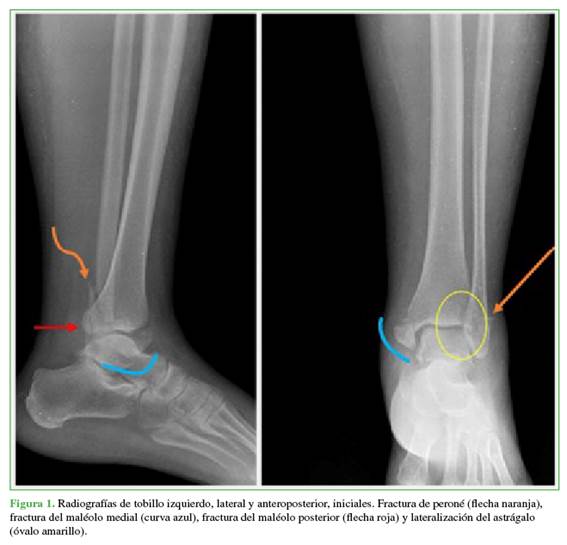

La paciente ingresó con radiografías simples anteroposterior y lateral del tobillo izquierdo que mostraban una fractura trimaleolar con traslación lateral del astrágalo (Figura 1). Luego de analizar las imágenes, se diagnosticó luxofractura trimaleolar del tobillo izquierdo. Se procedió a la reducción cerrada con sedación farmacológica a cargo del Servicio de Medicina de Urgencias. Se la inmovilizó con una férula posterior.